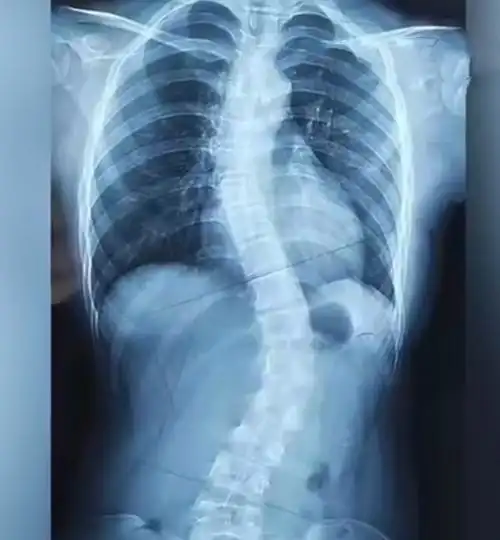

新苗脊柱侧弯医体治疗体系4060度治疗好转的病例